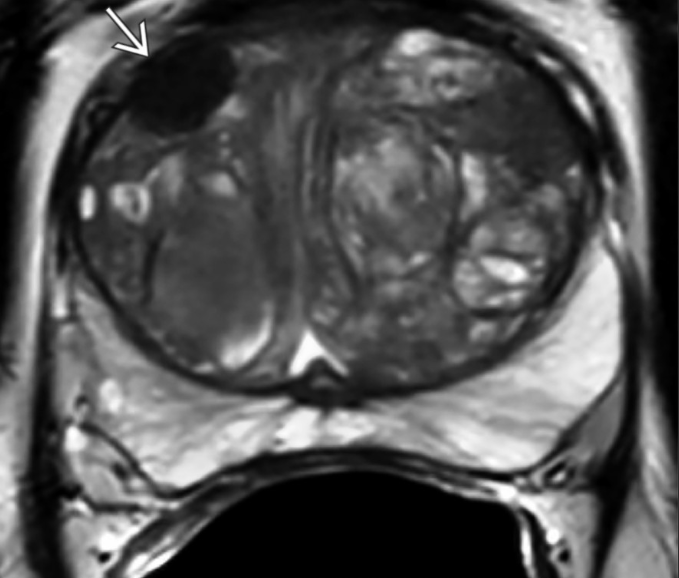

PI-RADS 2.

Nódulo anterior na zona de transição, hipointenso em T2, bem circunscrito e homogêneo, sem cápsula..